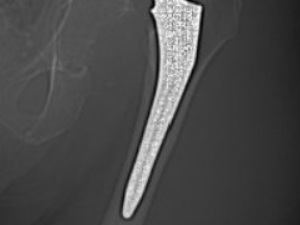

Cas 1. Luxation fémoro-acétabulaire de PTH

Cas 2. Luxation intra-prothétique de PTH